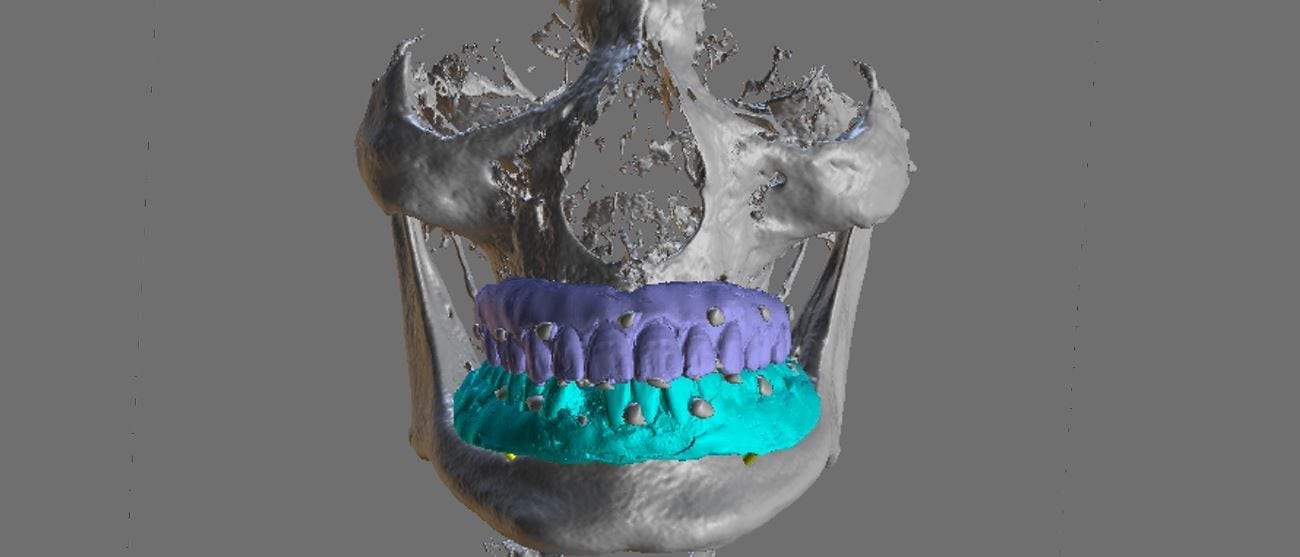

When planning for guided surgery in edentulous patients, it is important to have the final vertical dimension and tooth position determined. Ideally, a denture duplicate should be used with proper radiographic markers.

The traditional way was to embed radio-opaque material in the denture dupe, CT scan the patient with the denture dupes, and then CT scan the denture dupes themselves. Alternatively, you can scan the denture duplicates with a digital impression system. Here we used flowable composite and spread them through the wax set up and take a 3D X-ray of the patient. We then use those landmarks to merge the data sets between the digitize denture and the markers on the CT Scan

An important concept to keep in mind for these edentulous cases is that you actually need 2 models for each arch. One model is used for tooth positioning and implant design, and the other model is used for stent design. Essentially, you design the stent on the ridge, not the denture dupe